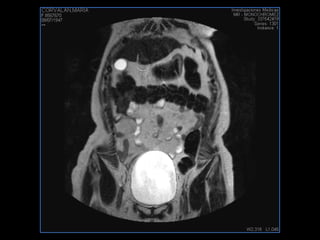

PROTOCOLO abdomen COR T2, AXIAL supresion grasa AX T1 +SAG T2  CON   GADOLINIO :  COR T1+AX T1(DIN) SAT: NO  FASE: RL THK: 6MM  COIL:  GAP: (FACTOR 1.4) 2MM FOV: 40 CM NEX:2 SINCRONIZACION RESPIRATORIA EN 3 O 4 CICLOS ALE

PROTOCOLO pelvis SAG T2, Y FAT SAT (FINOS) AXIAL T1  AX FAT SAT CON   GADOLINIO :  AX T1 Y COR T1 SAT: NO  FASE: RL THK: 3MM  COIL:  GAP: (FACTOR 1.4) 1MM FOV: 40 CM NEX:2 SINCRONIZACION RESPIRATORIA EN 3 O 4 CICLOS ALE

resonancia de abdomen